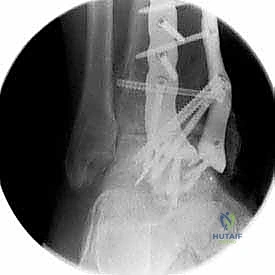

الخلاصة الطبية الشاملة: يُعد إجراء تثبيت مفصل الكاحل الأمامي (Anterior Ankle Arthrodesis) المعيار الذهبي والحل الجراحي الأكثر فاعلية لعلاج حالات خشونة الكاحل المزمنة والمتقدمة التي لم تعد تستجيب للعلاجات التحفظية. يهدف هذا التدخل الدقيق إلى إزالة الأنسجة الغضروفية التالفة ودمج عظام مفصل الكاحل (الظنبوب والكاحل) لتكوين كتلة عظمية واحدة صلبة ومستقرة. النتيجة المباشرة لهذا الإجراء هي القضاء التام على الألم المبرح واستعادة قدرة المريض على المشي وتحمل الوزن بثبات. يقدم الأستاذ الدكتور محمد هطيف، استشاري أول جراحة العظام والمفاصل وأستاذ جراحة العظام بجامعة صنعاء، هذا العلاج المتقدم بأعلى معايير الدقة العالمية، معتمداً على خبرة تتجاوز العشرين عاماً واستخدام أحدث تقنيات الجراحة الميكروسكوبية والمناظير، ليمنح المرضى فرصة حقيقية لاستعادة جودة حياتهم.

تثبيت مفصل الكاحل، أو "دمج الكاحل" (Ankle Fusion)، هو إجراء جراحي عالي التخصص يهدف إلى تحويل مفصل الكاحل المريض والمؤلم إلى كتلة عظمية واحدة صلبة وغير متحركة. الفلسفة الطبية وراء هذا الإجراء بسيطة وفعالة: "مفصل ثابت وبدون ألم أفضل بكثير من مفصل متحرك يسبب ألماً مبرحاً".

- تثبيت ميكانيكي حيوي أقوى: يتيح المدخل الأمامي وضع شريحة معدنية (Anterior Plate) على الجانب الأمامي للمفصل. من الناحية الميكانيكية الحيوية (Biomechanics)، يعتبر الجانب الأمامي هو "جانب الشد" (Tension side) أثناء المشي. وضع الشريحة هنا يوفر تثبيتاً فائق القوة ويقلل من معدلات عدم الالتئام.

خطوات جراحة تثبيت مفصل الكاحل الأمامي بالتفصيل (Step-by-Step Surgical Procedure)

تُجرى العملية تحت التخدير العام أو النصفي (الشوكي)، وتستغرق عادةً بين ساعتين إلى ثلاث ساعات، وتتطلب دقة ومهارة فائقتين. إليكم الخطوات الجراحية كما ينفذها الأستاذ الدكتور محمد هطيف: